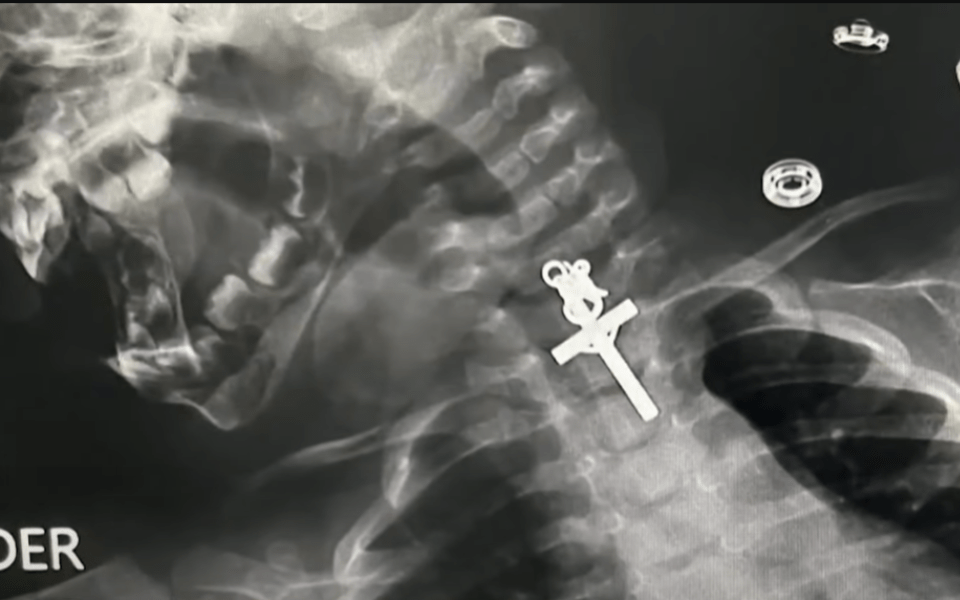

VIDEO: Descubren crucifijo en el interior de una bebé ...

Una menor de 10 meses fue llevada de urgencia a un hospital en Perú luego de tragarse un crucifijo que se alojó en su esófago. Al ser sometida a una radiografía que confirmó la presencia del objeto, los especialistas en gastroenterología le realizaron una endoscopía terapéutica para retirar el objeto dentro de la bebé. Tras la intervención, la madre agradeció a los médicos y catalogó la situación como un “milagro”.